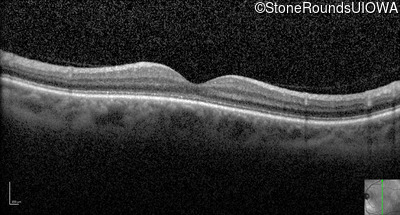

Optical Coherence Tomography - Right - 20/200 sc

Exemplar / OCT Stack